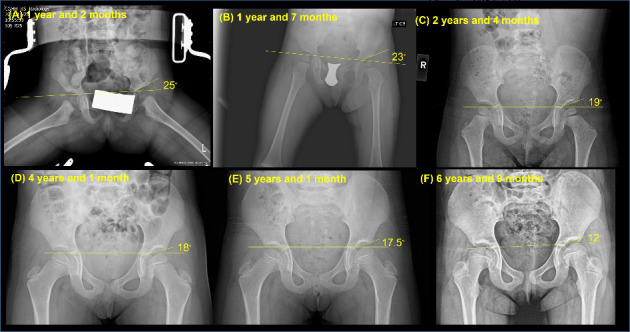

背景:迟发性髋关节发育不良(DDH)的诊断——定义为在8周龄后通过体格检查、超声或x线检查发现——发生在约0.14%-0.26%的婴儿中。本病例报告强调了延迟DDH诊断的挑战和物理治疗在康复中的作用。病例报告:患者为亚洲第一胎女性,妊娠40周顺产。她的早期病史包括左肌性斜颈、不对称哭脸综合征和喉软化。父母观察到不对称的臀沟,但3个月前的早期体检显示Barlow和Ortolani试验阴性,髋关节活动范围正常,无运动障碍。因此,由于身体检查结果阴性,缺乏典型的表现和体征,以及缺乏通常需要进一步影像学评估的主要危险因素,因此在婴儿早期超声成像被认为是不必要的。11个月时,负重减轻和腿长不一致的迹象导致x线检查,显示左DDH伴半脱位。治疗包括闭合复位、14周Spica石膏、14个月外展支具和物理治疗。铸造后,患者出现髋关节僵硬、活动受限和肌肉无力。物理治疗的重点是恢复运动,同时确保关节的稳定性。通过每周一次的治疗,患者取得了显著的进步,在19个月时实现了独立行走。随访x线片显示髋臼指数逐渐改善,在6岁零9个月时接近正常发育。结论:本病例强调了DDH早期检测的挑战,延迟诊断的后果,以及物理治疗在DDH患儿术后恢复和功能发展中的重要作用。

Background: Delayed diagnosis of developmental dysplasia of the hip (DDH)-defined as detection after 8 weeks of age using physical examination, ultrasound, or X-ray-occurs in approximately 0.14%-0.26% of infants. This case report highlights the challenges of delayed DDH diagnosis and the role of physical therapy in rehabilitation. Case Report: The patient, a firstborn Asian female, was born vaginally at 40 weeks gestation. Her early medical history included left muscular torticollis, asymmetric crying faces syndrome, and laryngomalacia. Parents observed asymmetric gluteal folds, but early physical examinations before 3 months showed negative Barlow and Ortolani tests, normal hip range of motion, and no motor impairments. Thus, ultrasound imaging was not deemed necessary in early infancy due to negative physical exam findings, the absence of classic presentations and signs, and a lack of major risk factors that would typically warrant further imaging evaluation. At 11 months, signs of reduced weight bearing and leg length discrepancy led to radiographic evaluation, revealing left DDH with subluxation. Treatment included closed reduction, 14 weeks in a Spica cast, 14 months of abduction bracing, and physical therapy. Following casting, the patient experienced hip stiffness, limited mobility, and muscle weakness. Physical therapy focused on restoring movement while ensuring joint stability. With weekly sessions, the patient showed significant progress, achieving independent walking at 19 months. Follow-up radiographs demonstrated gradual acetabular index improvement, approaching normal development by age 6 years and 9 months. Conclusion: This case highlights the challenges of early DDH detection, the consequences of delayed diagnosis, and the vital role of physical therapy in postoperative recovery and functional development of children with DDH.